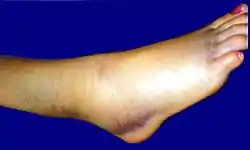

Артри́т голеносто́пного суста́ва — острый или хронический воспалительный процесс, характеризующийся болевым синдромом и нарушением подвижности (ощущение скованности). Область сустава становится отёчной, покрасневшей и горячей на ощупь.

При растяжении связок голеностопного сустава быстро развивается отек вследствие кровоизлияния с внутренней или наружной стороны сустава, появляются резкие боли при подвертывании стопы внутрь. При пальпации под лодыжками ощущается резкая болезненность. Если одновременно с растяжением связок происходит перелом V плюсневой кости, то определяется резкая боль при пальпации её основания.

Вывихи и подвывихи в голеностопном суставе комбинируются с переломами лодыжек. Вывих может возникнуть в месте соединения таранной и пяточной кости. В этом случае отмечаются значительное утолщение и деформация голеностопного сустава и пяточной области. Пятка подвернута внутрь.